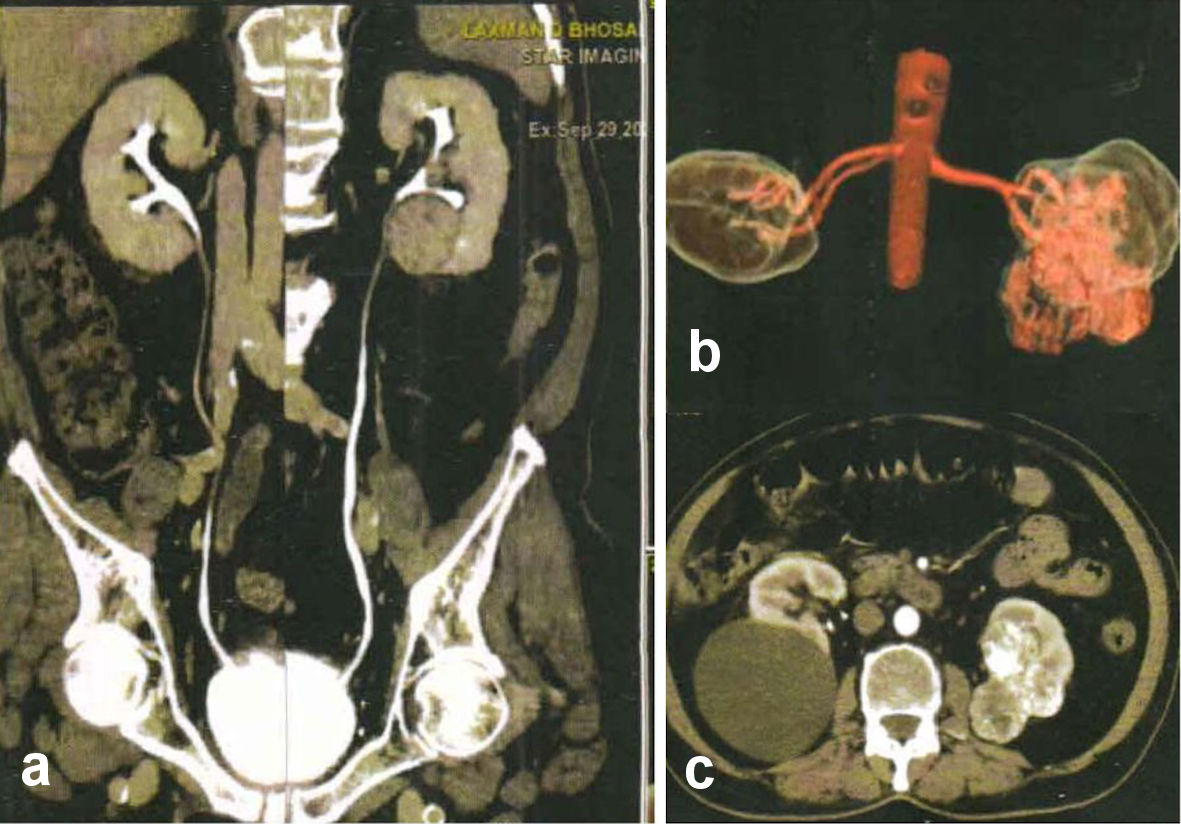

His sonography revealed a mass in lower pole of left kidney. CT showed a solid lobulated lesion at the lower and interpolar cortex of the left kidney with heterogeneous post contrast enhancement suggesting renal neoplasm. An exophytic cortical cyst at interpolar cortex of the right kidney was also noted. His biochemical profile was normal. Serum creatinine was 0.91 mg/dL.

Radionuclide renal scan was performed in conventional posterior view using 4 mCi of Tc-99m- DTPA administered intravenously with simultaneous acquisition of dynamic renal scan at the rate of 1 min per frame for 20 min. Siemens single head E-cam gamma camera system was used with low energy high resolution collimator. Split function was assessed using computer-generated renogram. Region of interest was drawn by an experienced operator. The split function calculated was 82% from the left kidney and 18%from the right kidney (Fig. 1a). As the structural appearance of the kidneys was quite normal on CT urography (Fig. 2a), and in view of a large cyst located on the posterior cortex of right kidney (Fig. 2b, c), the Tc-99m-DTPA renal scan was repeated in anterior view on another day.

![]() Click for large image | Figure 2. (a) Normal structural appearance of the kidneys on CT urography. (b, c) A large cyst located on the posterior cortex of right kidney. CT: computed tomography. |